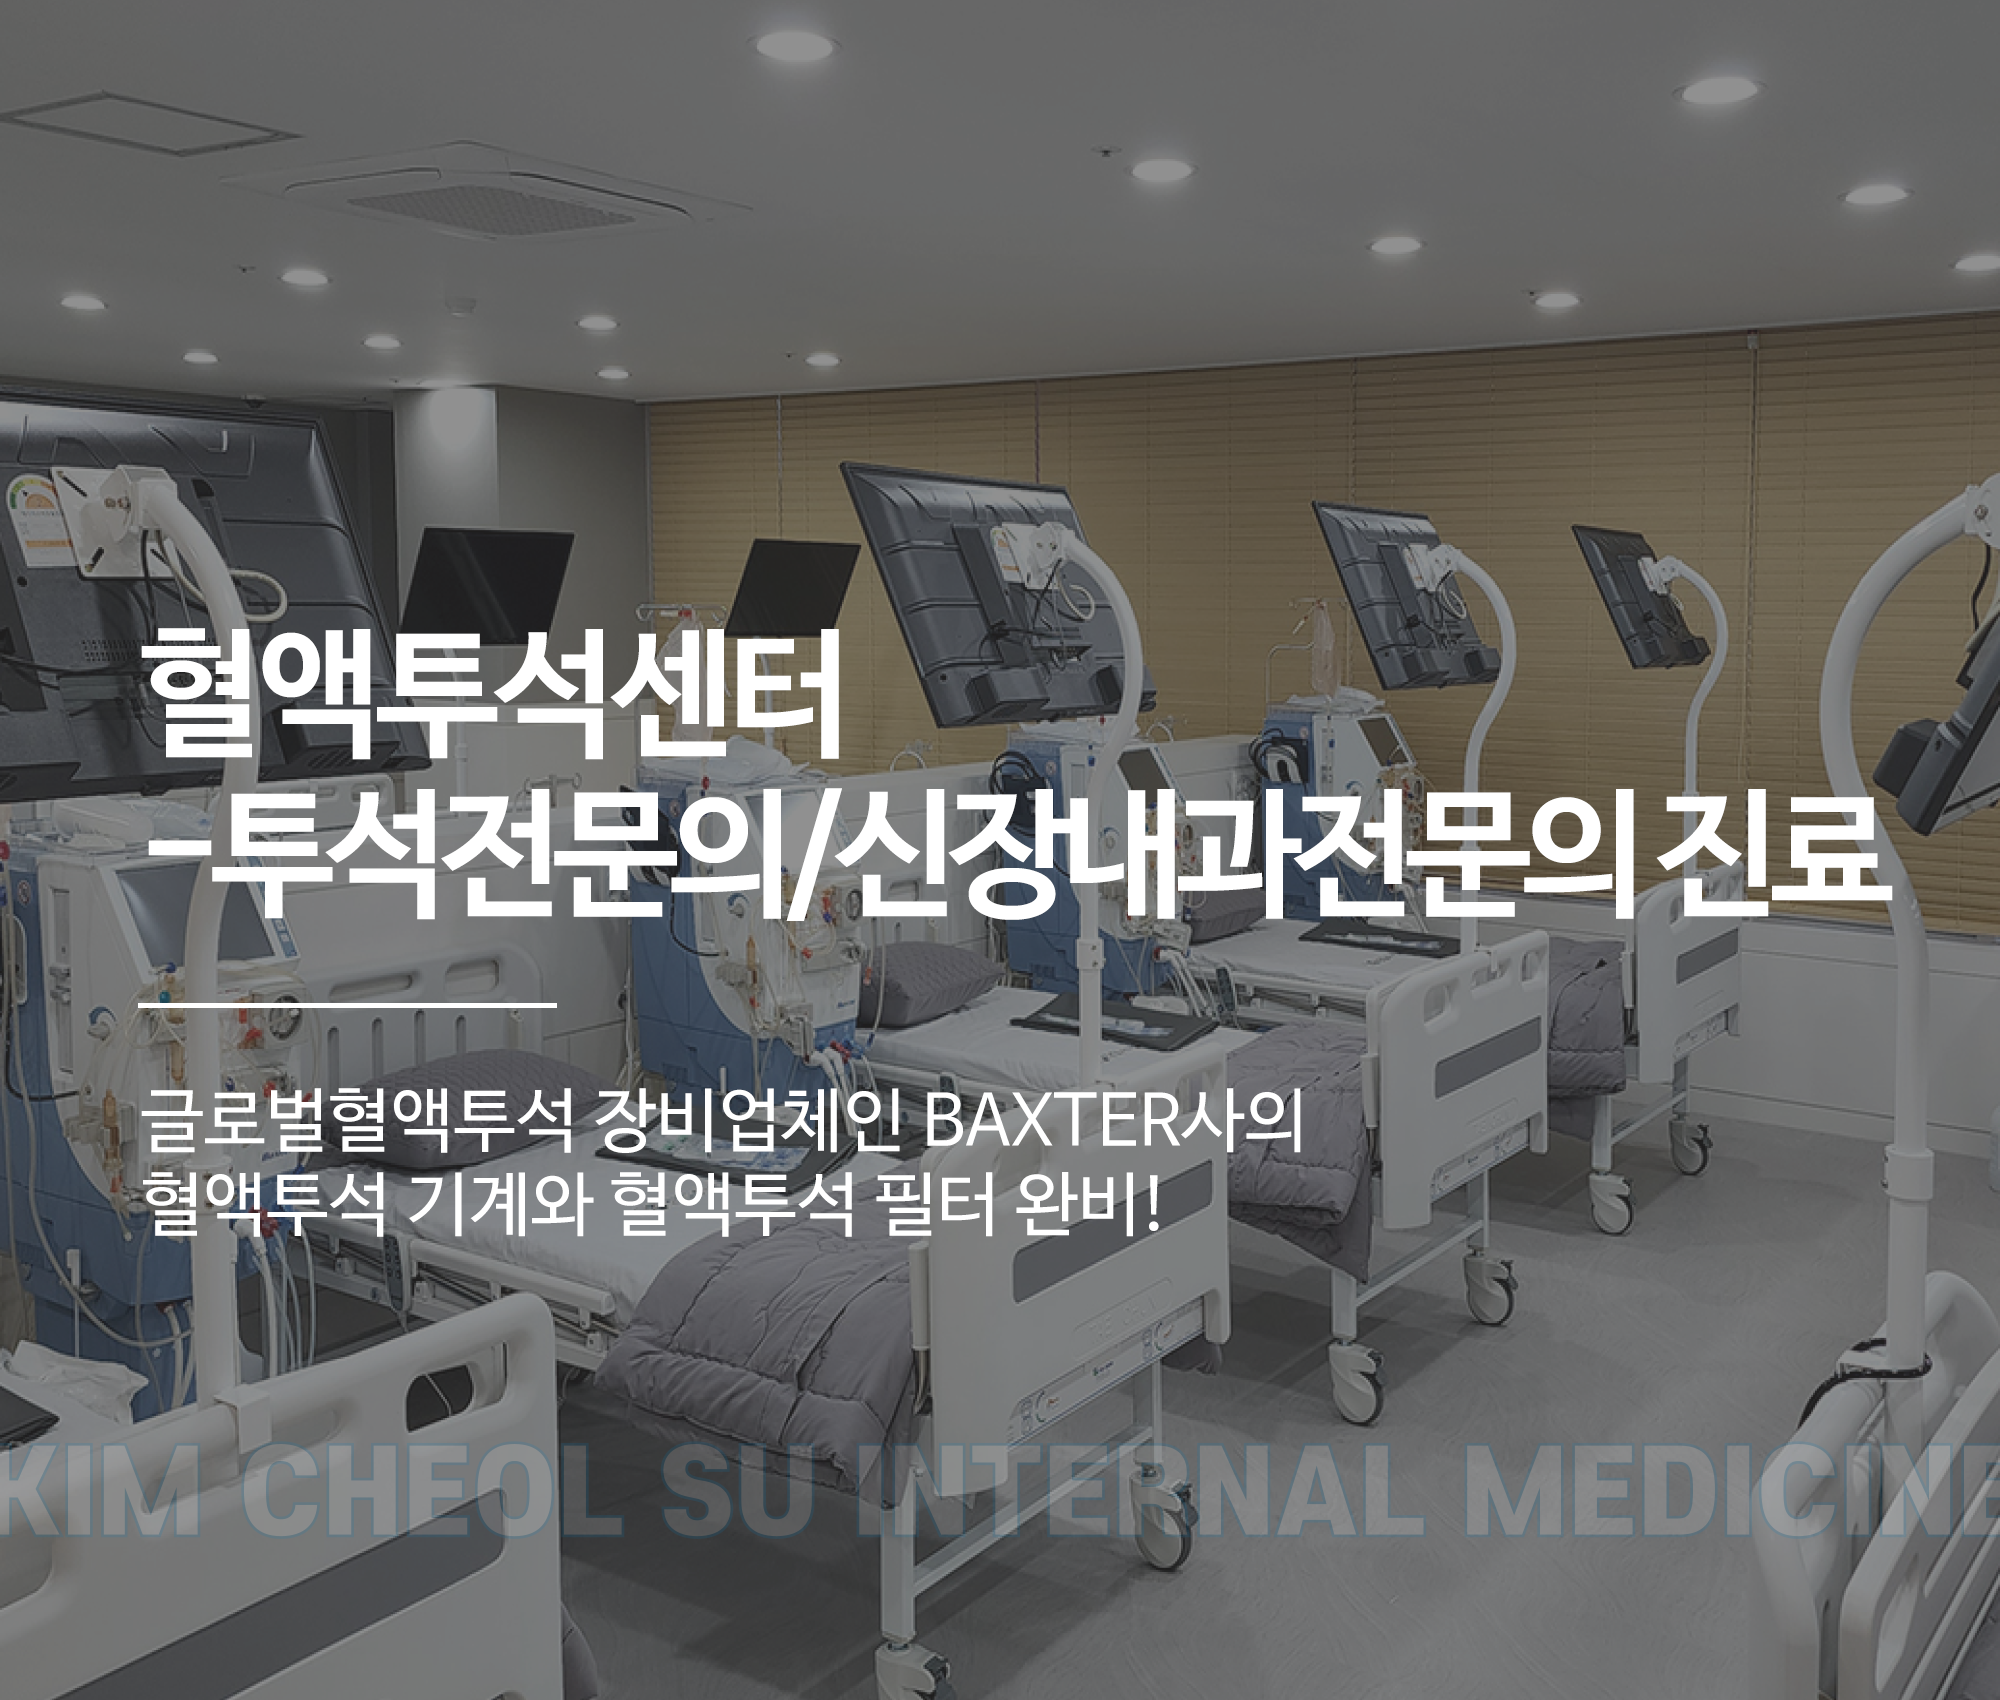

투석혈관 시술

- 투석혈관 협착, 투석혈관 막힘(혈전증) 치료, 투석도관 삽입 및 제거

투석전문의, 신장내과 분과전문의이면서 각종 혈관 시술 1,000례 이상의 경험을 보유한 김철수 원장이 직접 문제 진단 및 시술을 진행합니다.